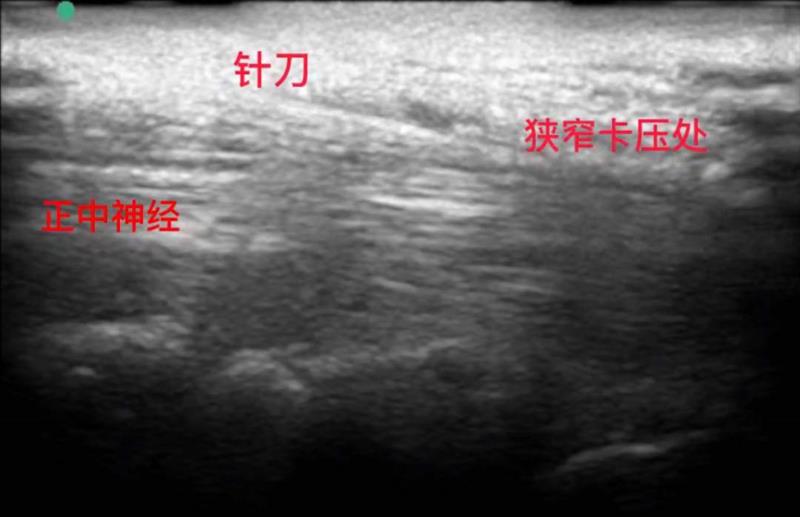

2. 针刀治疗:微创松解的“韧带疏通术”

作为中医微创技术的代表,可与超声引导注射联合使用,进一步提升治疗效果,尤其适用于腕横韧带增厚导致的腕管狭窄患者。

针对性强:通过微创针刀精准切断部分增厚的腕横韧带,直接扩大腕管容积,从根源上解除正中神经的压迫,比单纯药物注射更易实现长期缓解。

便捷高效:门诊即可完成治疗,局部麻醉下操作,全程创伤小、出血少,术后配合腕部制动和神经营养药物,1-2周即可缓解不适,无需住院治疗。

注意:针刀治疗需严格把控适应症,对于病史超1年、大鱼际肌明显萎缩、重度神经损伤患者,或合并凝血功能障碍、孕妇等,需评估后选择其他方案,避免风险。